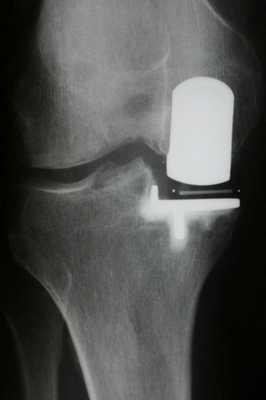

Имплант на рентгене.

Как это выглядит после операции.

Рентген после операции. Протез стоит корректно.